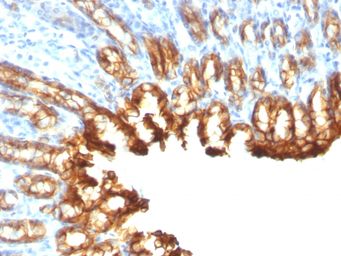

IHC-P analysis of rat stomach tissue using GTX34651 Cytokeratin 19 antibody [KRT19/800].